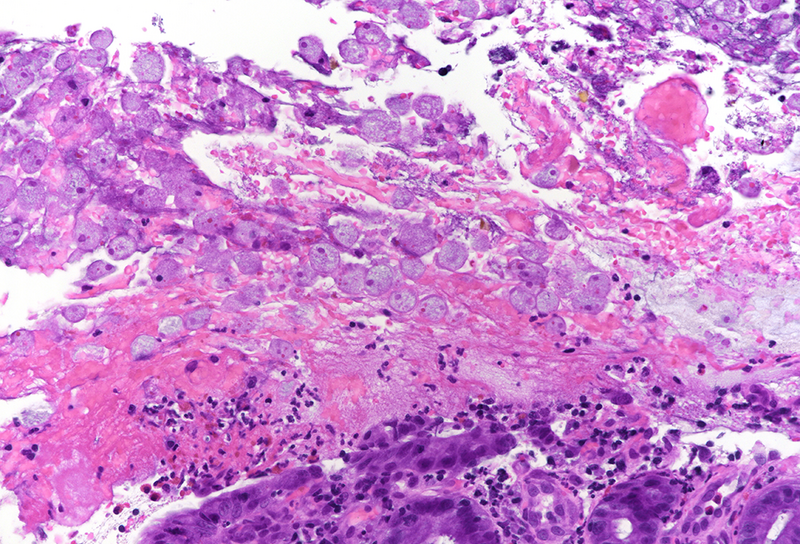

Histology revealed colonic mucosa with preserved architecture. Multiple erosions, crypts with degenerative features and increase of the inflammatory cell infiltrate in the lamina propria, especially granulocytes, were observed (PANEL A-B). On the luminal surface, accompanied by fibrin and debris, multiple organisms with roundish shape, foamy cytoplasm and round, pale and eccentric nuclei were found; some of those have erythrocytes engulfed in their cytoplasm (PANEL C-D); periodic acid-Shiff (PAS) stain highlights these organisms (PANEL E-F), which qualify for diagnosis of amoebiasis.

Histologically, initial lesions show a mild neutrophilic infiltrate, with numerous organisms present at the luminal surface associated with detritus. In advanced disease, ulcers are often deep, extending into the submucosa, sometimes with invasive amoebae within the bowel wall. Entamoeba histolytica has a roundish shape, with foamy cytoplasm and round, pale and eccentric nuclei with an open nuclear chromatin pattern. Within the inflammatory exudate, they may be difficult to distinguish from macrophages; in these cases, histochemical and immunohistochemical stains may be performed: amoebae are trichrome- and PAS-positive and macrophages stain with CD68. It is noteworthy the presence of ingested erythrocytes as pathognomonic feature of this parasite.